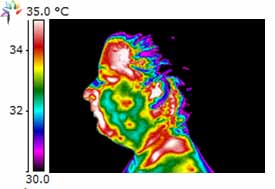

Dental Case Study 2

Patient exhibits Necrotic Molar in the lower left jaw.

Dental Case Study 3

Upper right 1st permolar – necrotic

Lower right bridge with necrotic tooth